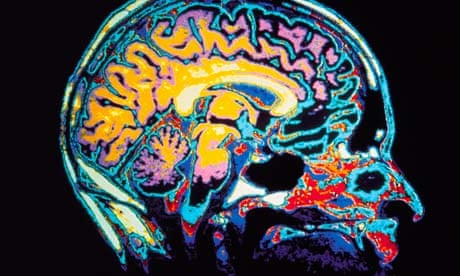

No dia 21 de Junho a revista Galileu publicou a seguinte notícia em seu site: "Comportamento antissocial é culpa do cérebro". Gostaria de fazer algumas considerações sobre esta matéria e também sobre a pesquisa lhe que serviu de base. Pois bem, um grupo de pesquisadores de diversos países, encabeçados pelo psicólogo inglês Graeme Fairchild, colocou 58 adolescentes diagnosticados com "transtorno de conduta" (grupo experimental) em uma máquina de ressonância magnética e mediu a espessura de 68 partes do córtex de seus cérebros, comparando-as com a de 25 adolescentes da mesma faixa etária não diagnosticados com o "transtorno" (grupo controle). E o que encontraram? De forma bem resumida, os pesquisadores apontaram para importantes diferenças entre os dois grupos no que diz respeito à estrutura cerebral. Mais especificamente, afirmaram ter encontrado significativas "diferenças quantitativas na organização estrutural" do cérebro tanto entre o grupo experimental e o grupo controle quanto dentro do próprio grupo experimental - que foi dividido em dois grupos: transtorno de conduta (1) com início na infância e (2) com início na adolescencia. Segundo os pesquisadores, o grupo experimental (1) apresentou mais semelhanças na espessura de diversas partes do córtex do que o grupo experimental (2) e do que o grupo controle, o que aponta para o entendimento de que adolescentes que desenvolveram transtorno de conduta quando crianças possuiriam um cérebro menos especializado ou diverso do que aqueles que desenvolveram o transtorno mais tarde e, especialmente, do que aqueles que não desenvolveram o transtorno. Os pesquisadores, entretanto, não compreendem ainda qual a relação entre menor especialização cortical e comportamento antissocial. E o que a revista Galileu, e até certo ponto o próprioFairchild neste texto, concluem dos resultados deste estudo? Que o "desvio de conduta" é um trantorno psiquiátrico real (e não uma uma "forma exagerada de rebelião adolescente") porque é causado pelo cérebro - que seria, então, o verdadeiro "culpado" pelo problema. Especialmente a revista, em sua ânsia de criar uma manchete bombástica, mas também o pesquisador ao tentar "traduzir" os resultados de sua pesquisa, cometem uma série de erros, que analisarei abaixo.

Em primeiro lugar, a revista e o pesquisador atribuem realidade somente àquilo que possuiria uma "realidade cerebral" - e com isso cometem um equívoco que o pesquisador Eric Racine chama de "neurorealismo", que é a crença de que encontrar alterações cerebrais provaria a existência ou a realidade de determinados sentimentos ou transtornos. Na verdade, descobrir que existem diferenças entre pessoas diagnosticadas e não-diagnosticadas não prova que este ou aquele transtorno é real. Aliás, o que isto significa? O que seria uma transtorno irreal? A partir do momento em que a Associação Psiquiátrica Americana (APA) escolhe classificar determinados comportamentos como "transtornos" e os insere no DSM, o diagnóstico passa a ser real. Não é a pesquisa neurocientífica que confere realidade ao transtorno, mas o consenso entre as "autoridades" de que se trata "realmente" de um transtorno. Esta ideia de que é o consenso que cria a realidade vale não só para transtornos psiquiátricos, mas para muitas outras coisas. Por exemplo: o amor é real? E o dinheiro? E as leis? A resposta para todas estas perguntas é sim, são reais, pois acreditamos que sejam. O amor, por exemplo, não tem qualquer realidade física, mas ninguém duvida de sua existência. Da mesma forma o dinheiro: uma nota de 10 reais não tem qualquer valor em si; seu valor é consequência de um consenso social de que aquilo possui de fato algum valor. O mesmo vale para as leis: elas existem porque acreditamos e agimos como se elas existissem. Tudo isto aponta para o fato de que a referida pesquisa não teria como conferir realidade ao transtorno de conduta, sendo possível apenas concluir que as pessoas previamente diagnosticadas com tal transtorno e que participaram do experimento, possuem determinadas caracteristicas cerebrais semelhantes - embora não exatamente iguais. Mas mesmo tal conclusão não pode ser generalizada para todas as pessoas com tal diagnóstico (e muito menos para todas as pessoas antissociais, tímidas ou problemáticas do mundo), em função do pequeno número de pessoas pesquisadas, apenas 58.

De toda forma - e este é o segundo e mais importante erro - isto não significa que são estas características cerebrais que causam determinado comportamento, por exemplo, o comportamento antissocial. É bem possível aliás, que ocorra o contrário: que o comportamento antissocial cause ou contribua para a constituição de determinadas características cerebrais. Peguemos uma outra situação: imaginemos que cientistas coloquem pessoas anoréxicas em um equipamente de ressonância magnética e encontrem, comparativamente com um grupo não-anoréxico, uma maior "ativação" de determinadas áreas do cérebro. Isto significa que são estas áreas que causam a anorexia ou que, por exemplo, a falta de uma alimentação adequada afeta a "ativação" de tais áreas? Ou então imaginemos que cientistas coloquem pessoas apaixonadas em um moderno equipamento de tomografia e constatem, após exibir para elas uma série de imagens da pessoa amada, que determinadas áreas são "ativadas". Isto significa que são estas áreas que causam a paixão? Ou quer dizer, pelo contrário, que a ativação destas áreas é consequência desta paixão? Dizer que o cérebro causa tal ou qual comportamento ou, pior, que "a culpa é do cérebro", é um erro primário, que cientistas costumam evitar (nem sempre), mas que jornalistas e divulgadores científicos cometem todos os dias. Este argumento simplista de que a "culpa é do cérebro" também tem sido constantemente usado nos tribunais por advogados de defesa na criação de justificativas para determinados crimes (este video do Porta dos Fundos, embora trate da utilização da astrologia no tribunal, ironiza justamente estas explicações que tentam anular a responsabilidade do indivíduo por suas ações). Em comum entre advogados e divulgadores científicos está, neste caso, o entendimento de que é o cérebro que causa a mente e o comportamento. O grande problema destas explicações supostamente neurocientíficas é que elas ignoram a própria neurociência e os neurocientistas contemporâneos, que tem disseminado um entendimento muito menos determinista e mais dinâmico do cérebro e da mente. A ideia de plasticidade cerebral aponta justamente para o entendimento de que não só o cérebro "causa" a mente e o comportamento, mas também que estes "causam" mudanças no cérebro. Isto significa que, exceto em casos muito graves e raros, não é o cérebro o único responsável por nossas ações. Como afirmam Sally Satel e Scott Lilienfeld, no sensacional livro Brainwhashed: the seductive appeal of mindless neuroscience, "nossas decisões são inevitavelmente produto de uma vasta gama de influências - nossos genes (e a história evolucionária que eles representam), os mecanismos dos nossos cérebros, nossa criação, assim como o ambiente físico e social em que vivemos". Todas estas forças convergem para a produção de nossos pensamentos e ações. O cérebro é "apenas" mais um elemento em cena.